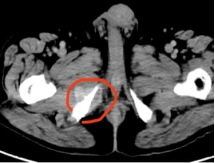

▲ 术前PET提示右侧坐骨转移

▲ 术前CT检查提示多发骨转移